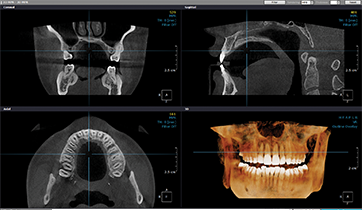

精密診断です。

3D CT撮影

口腔精密検査です。

全身の健康状態です。

体系的診断です。